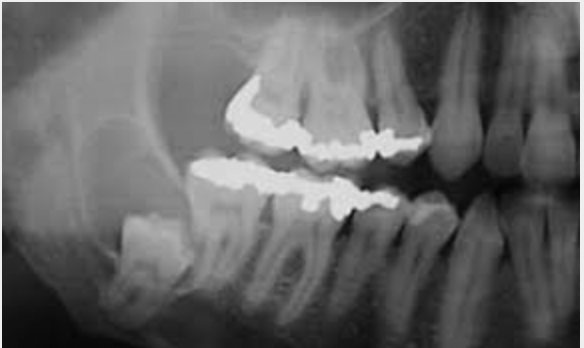

1. How does it appear histologically and radiographically? radicular cyst.

Radiographically

- Unilocular radiolucent round lesion centred around the apex of a non-vital tooth (has evidence of loss of vitality carious, extensive restoration previous RCT etc)

- Well differentiated corticated margin (which is continous with the lamina dura on either side of the root)